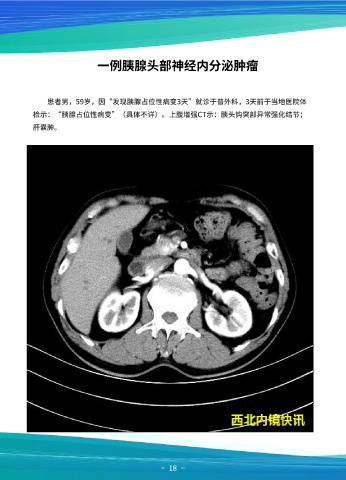

患者男,59岁,因“发现胰腺占位性病变3天”就诊于普外科,3天前于当地医院体 肿瘤。患者行剖腹探查、胰十二指肠切除术,术后病理回报:胰头部神经内分泌瘤(G2

检示:“胰腺占位性病变”(具体不详)。上腹增强CT示:胰头钩突部异常强化结节; 型),各切缘未见瘤组织,胆囊示轻度炎症改变。

肝囊肿。